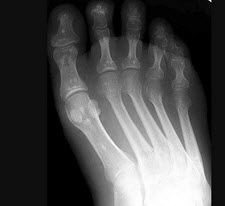

D.感染性

女,3岁,身体发育异常,如图所示,最可能的诊断为()